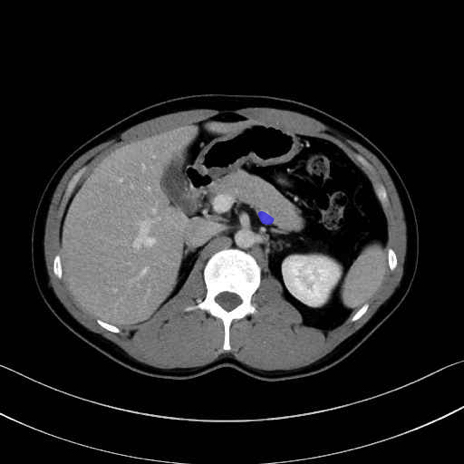

脾静脈の画像解剖

■起始:脾門で脾静脈枝が合流して本幹を形成。

■走行:膵体尾部の後面溝を右走し、膵頸部の後方で上腸間膜静脈(SMV)と合流して門脈を形成。

■主な流入枝:短胃静脈・左胃大網静脈・膵静脈、そして下腸間膜静脈(IMV)(変異あり)。